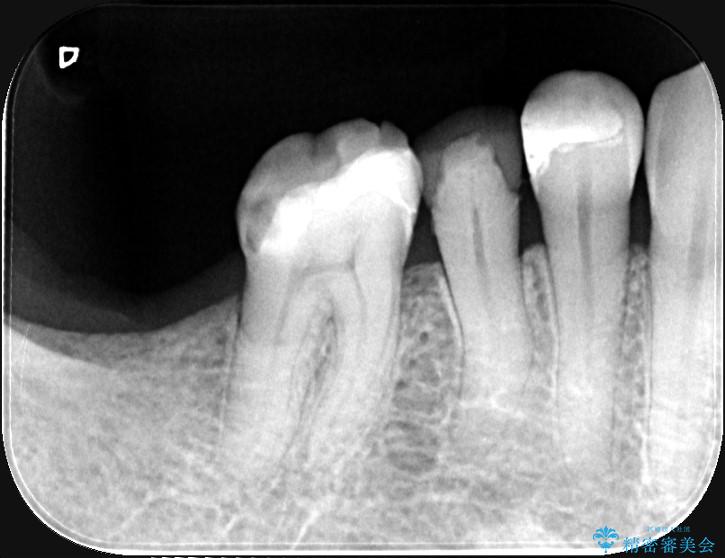

MOD窩洞のように欠損範囲が大きい場合、インレーでは咬合力に対する耐久性が不足し、破折リスクが高くなるケースがあります。

歯の中央から両側にかけて大きく削られている(MOD窩洞)状態でした。

噛む力がかかることで、インレーでは負担に耐えきれず破折してしまったと考えられます。

このようなケースでは、部分的に詰める治療よりも歯全体を覆うクラウンの方が強度的に有利です。